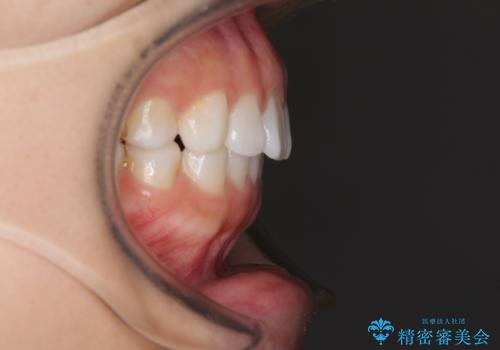

インビザラインによる軽度な出っ歯の矯正治療

- 上の前歯の出っ歯を治したいとのことで来院された患者様です。

上下顎ともにIPR(歯と歯の間を削る)と歯列全体の拡大によって口元が引っ込むように設計し、インビザラインにより治療を行うこととしました。

どこまで口元を引っ込めることができるのか、患者様自身も正直分からない部分があったため、少しずつ治療ゴールを変更しながら仕上げていきました。

気になっていた前歯の飛び出した印象は、最終的にはスッキリと引っ込み、大変満足していただきました。